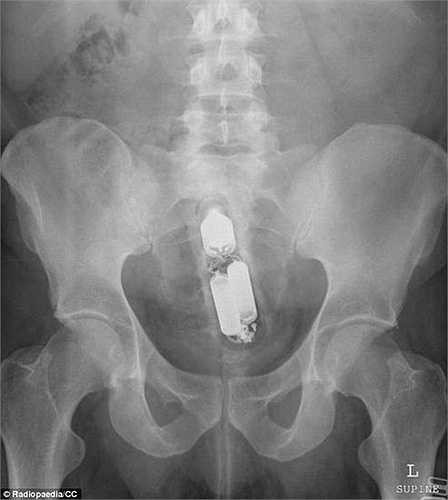

Trường hợp khác, sex-toy được đưa vào quá sâu bên trong âm đạo một phụ nữ.